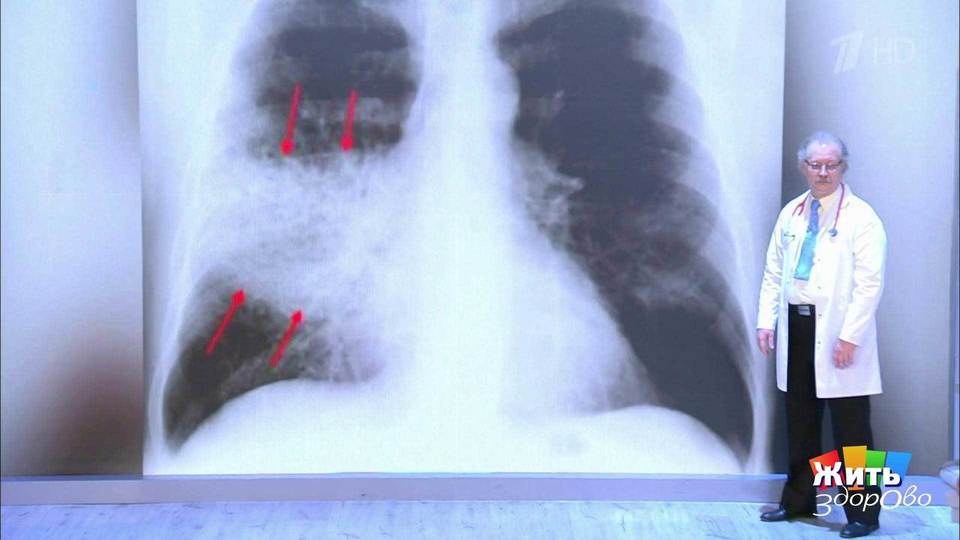

Для диагностики пневмонии нужно сделать КТ или рентген легких, а также сдать специальные анализы.

При вирусной пневмонии воздух есть в альвеолах, но в сосудах вокруг альвеол появляются микротромбы, а также появляется утолщение стенок альвеол. При такой пневмонии на КТ легких можно увидеть «матовое стекло». Обычно такая пневмония гораздо менее опасна, чем бактериальная, так как при «матовом стекле» может сохраняться функция дыхания.

Нужно помнить, что «матовое стекло» не всегда свидетельствует о наличии вирусной пневмонии, например, такое стекло может появиться из-за застоя крови в легких при сердечной недостаточности.